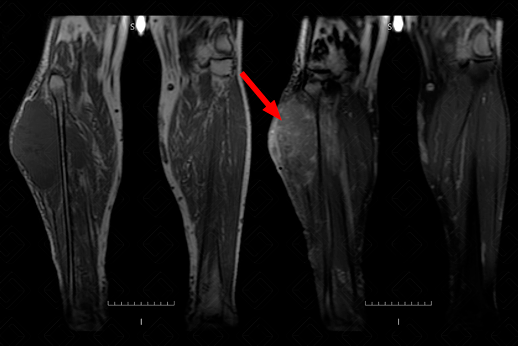

Texto alternativo para a imagem Figura 1. Créditos: Athena Hub/Medical Harbour

Descrição da figura 1: Ressonância magnética dos membros inferiores, T2. Lesão na face lateral do membro inferior direito, envolvendo os planos musculares e adiposos, com hipersinal homogêneo em T2 (seta vermelha).

O grau histológico dos sarcomas de partes moles é o principal fator envolvido no prognóstico do paciente. Alguns achados de imagem na ressonância magnética podem sugerir tratar-se de um tumor de alto grau (grau III): realce pós-contraste peritumoral, heterogeneidade de sinal em T2 envolvendo pelo menos 50% da área tumoral e presença de área necrótica (figuras 1 e 2).